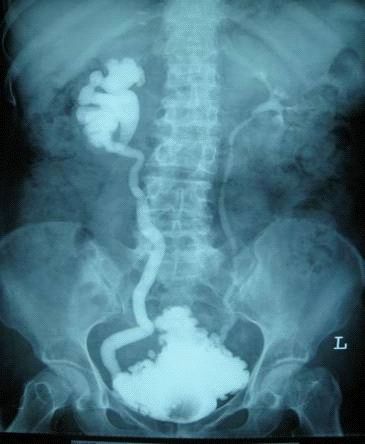

脊髓损伤影像学诊断

脊髓损伤平面诊断